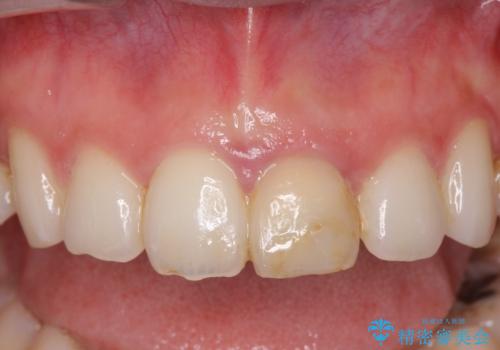

根管治療は行わず、仮歯・ジルコニアクラウンのみの処置を行い自然な歯に仕上げることができました。